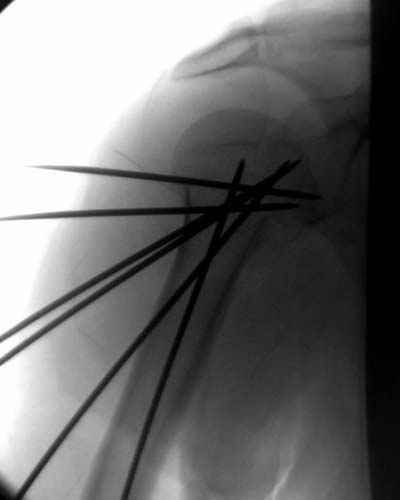

Посылаю послеоперационные Рг граммы.

Всего Доброго,

Поздравляю, получилось просто замечательно. Если можно, расскажи чуть подробнее, как делали - как вправляли, как вводили спицы, поворачивали ли их?

|

Спасибо за поздравления:-))

Я и сам доволен результатом. В предпоследнем письме я кратко описал ход операции - закрыто репонировать не удалось( 2 недели с момента травмы и 1 неделя после неудачной репозиции) после удаления пучков спиц, пришлось сделать - 2см разрез на уровне перелома и с помощью периостального элеватора (золотое правило механики) *одеть* головку на дистальный отломок.

Спицы проводил через старые отверстия, вращая пучок импактором- направителем при его введении в головку.